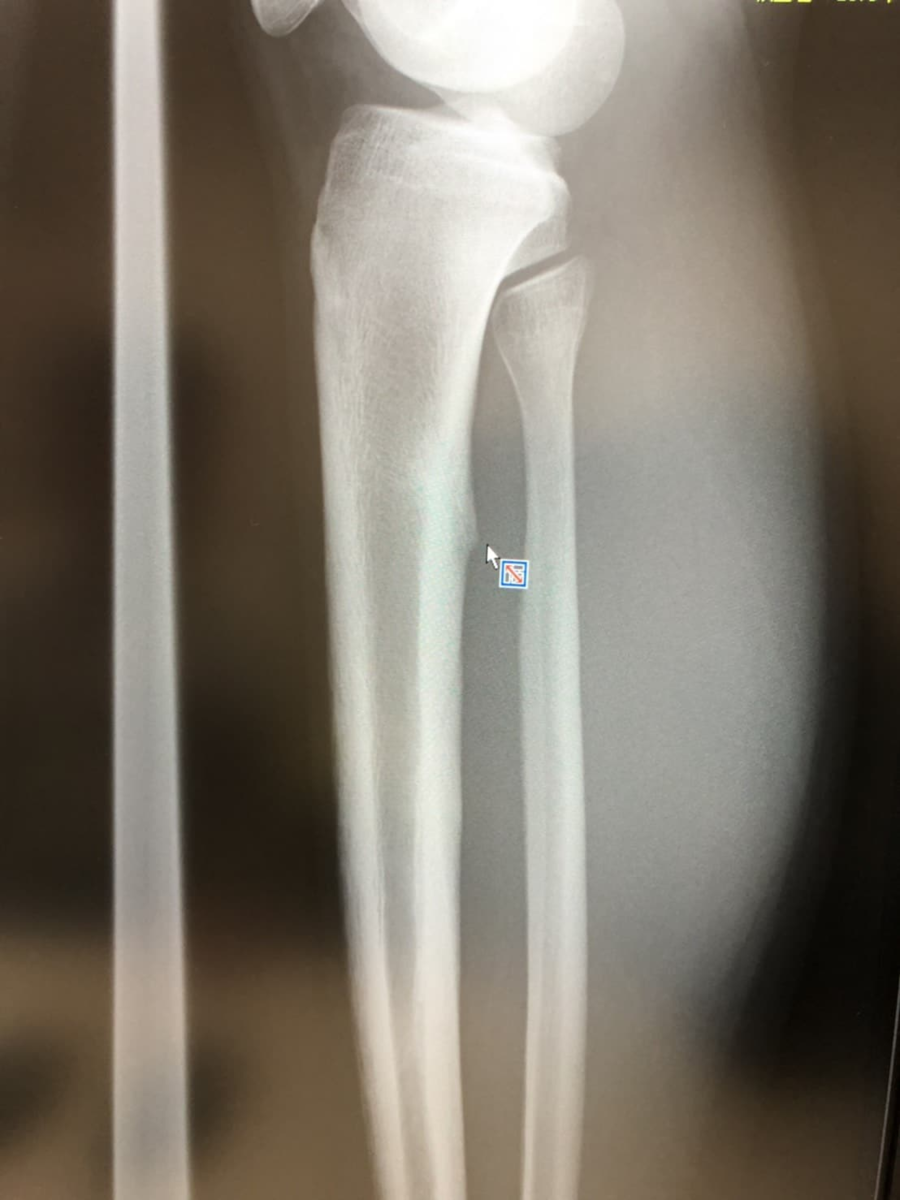

前回の整形外科ではレントゲン無し、診察もふくらはぎ部分のみでしたが、今回はレントゲンも撮ってもらいました。医師の診察によると、「疲労骨折(しかも複数)」という診断でした。上の写真はぼくのレントゲンではありませんが、まさにこんな感じで骨に小さな突起が2か所くらいできていました。普通骨の表面は平らなんですが、疲労骨折して治った所がこのように小さな盛り上がり形状になるらしいです。

レントゲン見たところ2か所くらい治った後の突起があり、今一番痛い部分にまだ治っていないと思われるエリアがありました。(完全に直ると白く写りますが、治っていないとちょっと黒っぽく写ります。)この影響で周囲の筋肉が炎症を起こしているらしく、エコーで見せてもらいました。